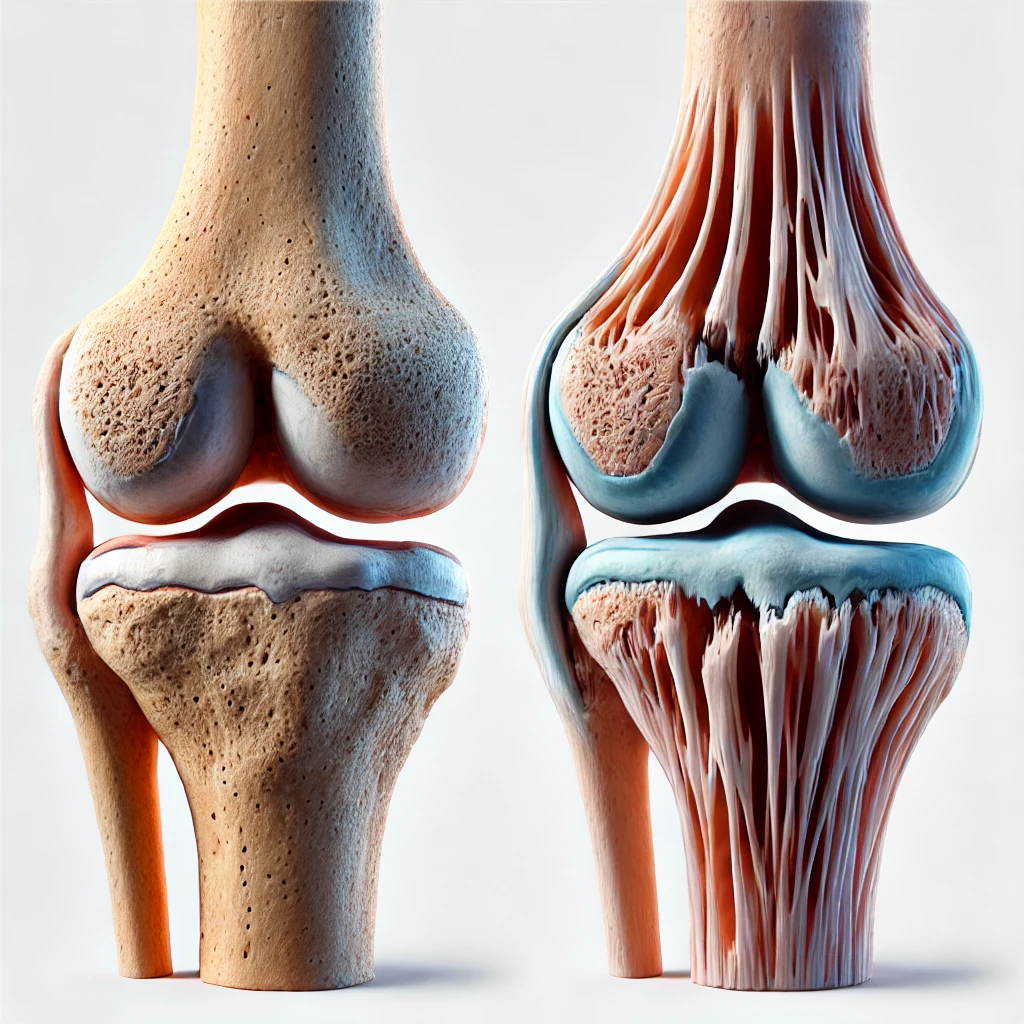

관절의 윤활제 역할

콘드로이친은 관절의 윤활제 역할을 하여 관절의 움직임을 부드럽게 만듭니다. 이는 특히 나이가 들면서 관절이 뻣뻣해지는 중장년층에게 큰 도움이 됩니다.

통증 완화

염증을 억제하는 효과가 있어 관절 통증을 줄이는 데 기여합니다. 지속적인 관절 통증으로 고통받는 분들에게 좋은 선택이 될 수 있습니다.